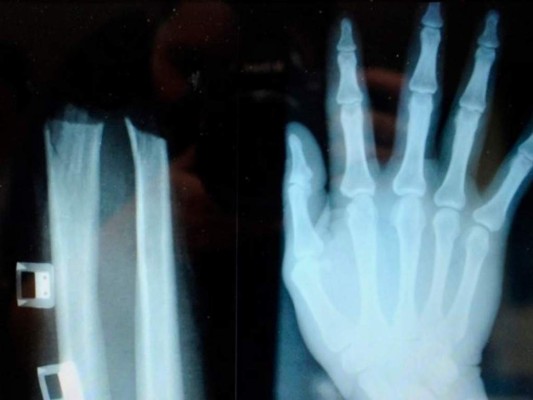

Julija Adlesic, que terminó con una mano completamente seccionada hasta la muñeca, fue acusada de haber escenificado, con tres cómplices, un accidente para recibir una indemnización de 380,000 euros y de 3,000 euros al mes hasta el final de su vida, según la policía.

Julija Adlesic fue llevada luego por sus cómplices al hospital sin su mano cortada, ya que el grupo tenía la intención de cobrar indemnizaciones más elevadas por una invalidez permanente, precisó la policía.

Pero la mano fue recuperada a tiempo y cosida en un hospital de Liubliana.